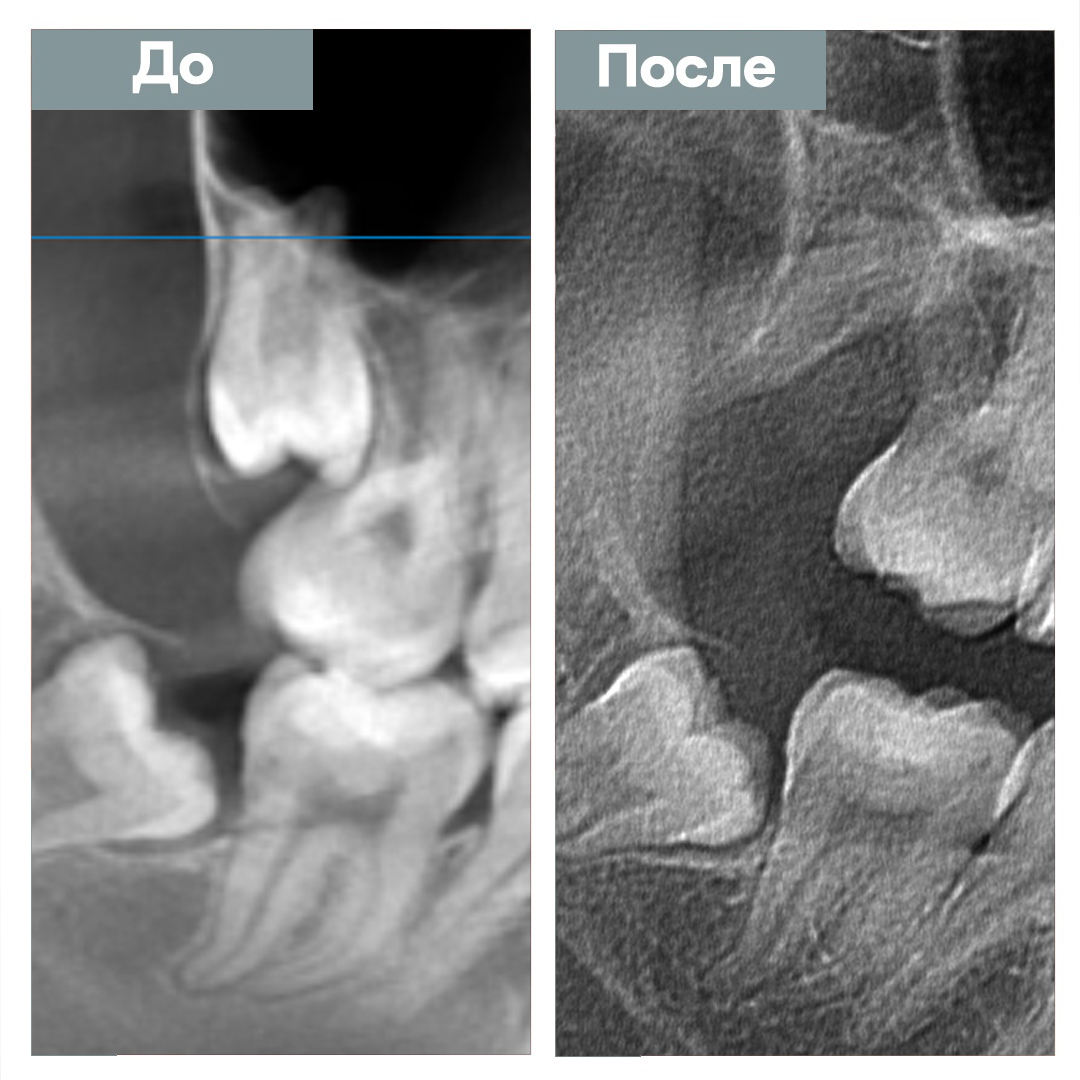

Удаление ретинированного зуба